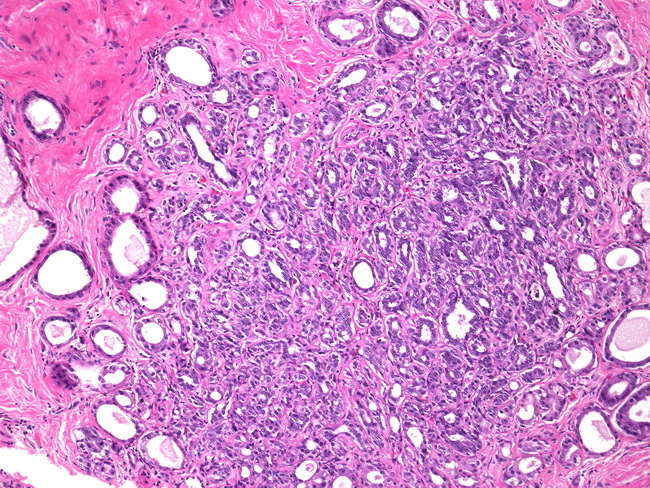

A

Phyllodes tumor

Biphasic tumor composed of spindled stromal cells and benign epithelial cells. Stromal cellularity is variable, and ranges from paucicellular to hypercellular. Prominent and exaggerated intracanalicular pattern with “leaf-like” projections into variably dilated lumina.

Shown is a malignant phyllodes tumor. The stroma is diffusely hypercellular with pleomorphic cells, mitotic figures, and necrosis. “Stromal overgrowth” (where you can find fields of stroma only) is suggestive of malignancy as well.

Increased incidence in Li Fraumeni syndrome. Presents as a palpable, painless breast mass. Can have heterologous elements that are malignant.

Molecular: MED12 and RARA mutations in benign phyllodes tumors.

TERT promoter, ERBB4, TP53, EGFR, PIK3CA, and RB1 in borderline or malignant phyllodes tumors.